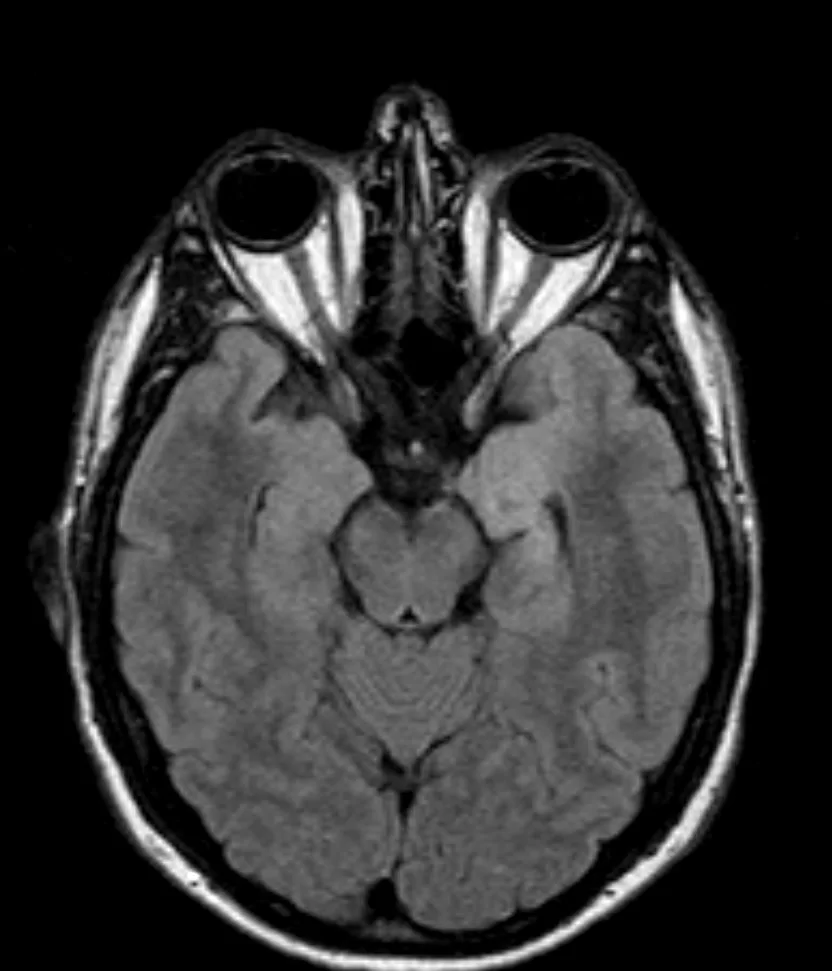

Ο απεικονιστικός έλεγχος με μαγνητική τομογραφία ανέδειξε πάχυνση του αριστερού ιπποκάμπου και της αμυγδαλής με μικροφυσαλλιδώδη στοιχεία. Στη διαφορική διάγνωση ετέθη το χαμηλόβαθμο γλοίωμα, το DNET και η σκλήρυνση του ιπποκάμπου.